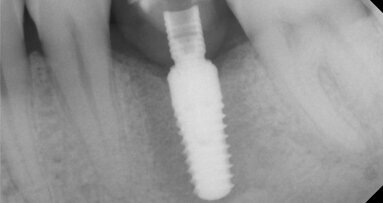

Po diskuzi s pacientem se v rámci možností náhrady zubu 16 rozhodl pro variantu nesenou implantátem. S pomocí operační šablony zajišťující správnou pozici pilotního vrtáku byl zaveden implantát MegaGen AnyRidge 4 × 10 mm. Za využití MegaGen fuse abutmentu a materiálu DMG Luxatemp byla následně zhotovena provizorní korunka. Poté byl z diagnostického wax-upu zhotoven silikonový klíč a dočasná korunka byla vyleštěna a vyřazena z okluze, aby bylo umožněno plné vhojení implantátu (obr. 3).

Po 3měsíční vhojovací fázi se pacient dostavil zpět pro osazení implantátu definitivní korunkou. V průběhu této doby měly měkké tkáně okolo implantátu prostor se formovat, díky čemuž kolem něj vytvořily krásný tvar (obr. 4, 5).